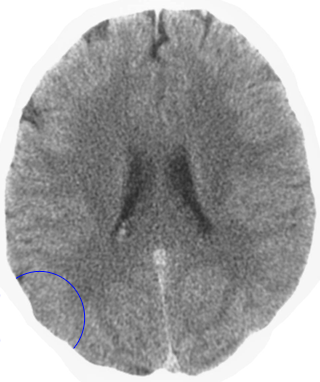

Which is the brain relais that is shown here? 25 Questions each cycle, try more!

Question 1 of 25

Middle ear mucosa left

Rectal mucosa

Coronary arteries, aortic arch, carotid arteries, bradycardia, penile sensitivity, clitoral sensitivity

Liver

Left hemispheres of the retinas

Lesser curvature of the stomach, mucosa of the bile ducts, pancreatic ducts, bulb of the duodenum